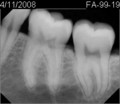

• 762DC845-7A44-4941-A538-B76BD8616145.jpeg

762DC845-7A44-4941-A538-B76BD8616145.jpeg

11.6 KB · Views: 5